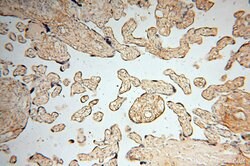

| Immunohistochemistry (Paraffin) | |

| Human, Mouse, Rat | |